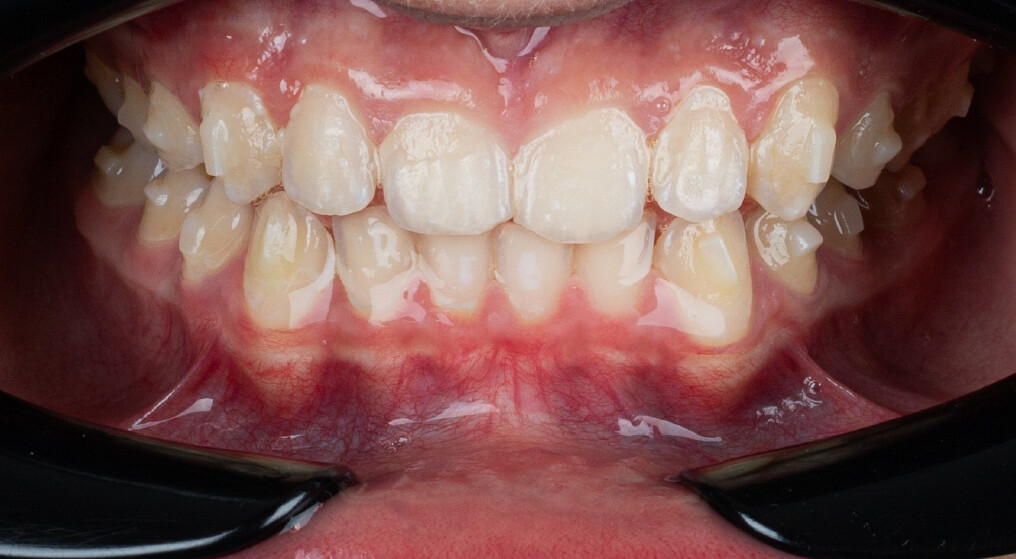

Um paciente do sexo masculino, com 13 anos de idade, apresentou-se com uma mordida profunda, caracterizada pela cobertura quase completa dos incisivos mandibulares. A avaliação clínica revelou apinhamento em ambas as arcadas, rotações dentárias e proclinação dos incisivos laterais superiores, contribuindo para as preocupações estéticas do paciente. O perfil facial era retrusivo, consistente com retrognatismo mandibular, e não foram detectadas anomalias periodontais significativas.

O paciente apresentava uma relação esquelética de Classe II com molares e caninos bilaterais em Classe II e um padrão dentário de Classe II divisão 2. A mordida profunda estava associada a um apinhamento anteroinferior e a uma curva de Spee acentuada. A análise facial revelou boa simetria, um terço facial inferior ligeiramente aumentado e um perfil convexo caracterizado por retrusão mandibular e do mento. A competência labial estava ligeiramente reduzida, com diminuição do ângulo nasolabial e leve tensão do músculo mentoniano, fatores que comprometiam a harmonia facial global.

- Intrusão programada dos incisivos centrais superiores para reduzir a exposição gengival e corrigir o sorriso gengival;